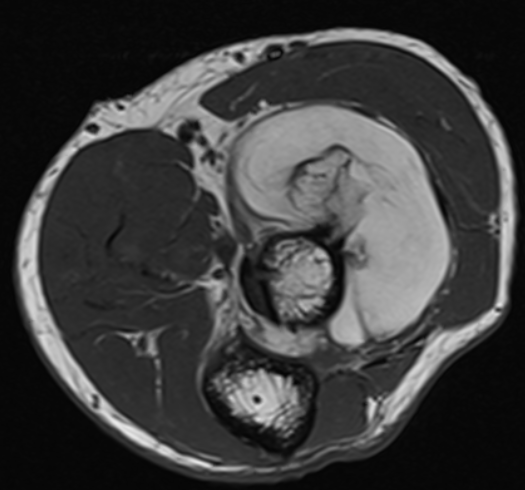

3. Osseous lipoma